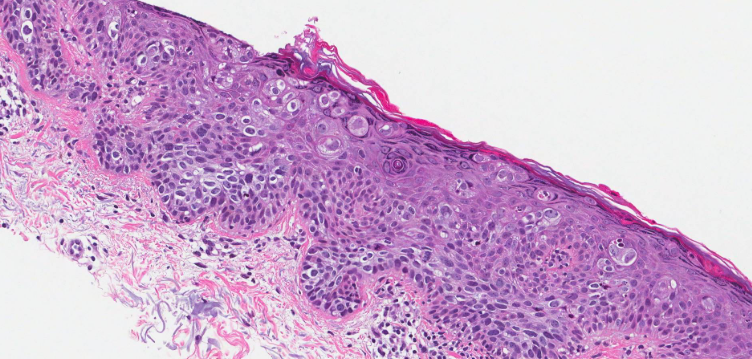

제자리암은 영어로 Carcinoma in situ라고 하며, 말 그대로 ‘제자리에 있는 암’을 의미합니다. 암세포가 생기긴 했지만, 기저막을 뚫지 않아 주변 조직으로 퍼지지 않은 상태를 말합니다. 이 단계에서는 세포가 비정상적으로 변했지만, 혈관이나 림프를 통해 다른 부위로 전이되지는 않습니다.

제자리암과 침윤암의 가장 큰 차이는 ‘퍼짐의 유무’입니다. 제자리암은 세포가 변형되었으나, 그 변화가 한정된 부위에 머무는 상태입니다. 반면 침윤암은 세포가 기저막을 넘어 주변 조직, 림프, 혈관 등으로 퍼진 상태를 말합니다. 따라서 침윤암은 수술, 항암, 방사선 치료 등 적극적 치료가 필요하지만, 제자리암은 비교적 관리 중심으로 접근할 수 있습니다.

제자리암은 건강검진이나 정기 세포검사에서 우연히 발견되는 경우가 많습니다. 대부분 증상이 없기 때문입니다. 예를 들어 자궁경부 제자리암은 자궁경부 세포검사(Pap smear)에서 비정상 세포로 확인되고, 조직검사로 확진됩니다. 유방 제자리암 역시 유방촬영이나 초음파에서 미세석회화 병변으로 나타나 진단됩니다.